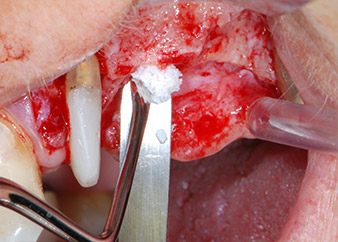

Avant la mise en place de l'implant, et après vérification de l'intégrité de la membrane de Schneider (Fig. 9), le plancher sinusien interne a été élevé sur les deux sites d'implantation à l'aide d'un matériau de substitution osseuse xénogénique (Bio-Oss, Geistlich Biomaterials) (Fig. 10).

Les défauts osseux autour des implants, sur la face mésiale de la dent 27 et autour de la racine de la dent 24, ont été reconstruits par des particules de substitut osseux xénogénique et recouverts d'une membrane collagène résorbable (Bio-Gide, Geistlich Biomaterials) pour une augmentation par GBR (Fig. 13 et 14).